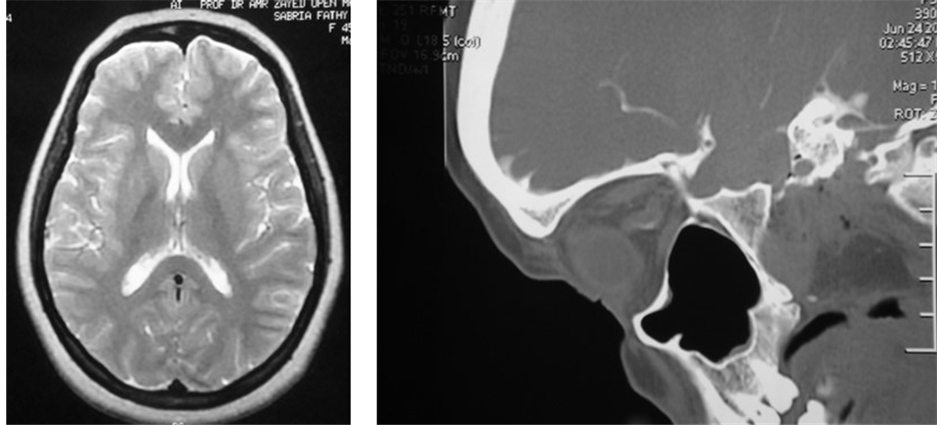

The radiological data suspicious of increased intracranial pressure were looked for in CT scan and MRI. All patients had empty sella syndrome (100%) whether partial or complete (Figure 3). Ten patients had slit-like ventricles and tight subarachnoid spaces, while only 5 patients had tortuous optic nerve (Figure 4).

Figure 4. Radiologic criteria of elevated ICP (a) T2 weighted MRI showing slit-like ventricles and tight subarachnoid spaces (b) Sagittal CT scan showing tortuous optic nerve.